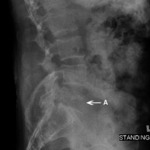

Radiograph of tumor: lymphoma (A) destroying the L5 vertebra

Courtesy of Dr K. Singh; used with permission

Radiograph of a compression fracture: a lateral radiograph of an L2 compression fracture (A). Wedging of the vertebral body is seen